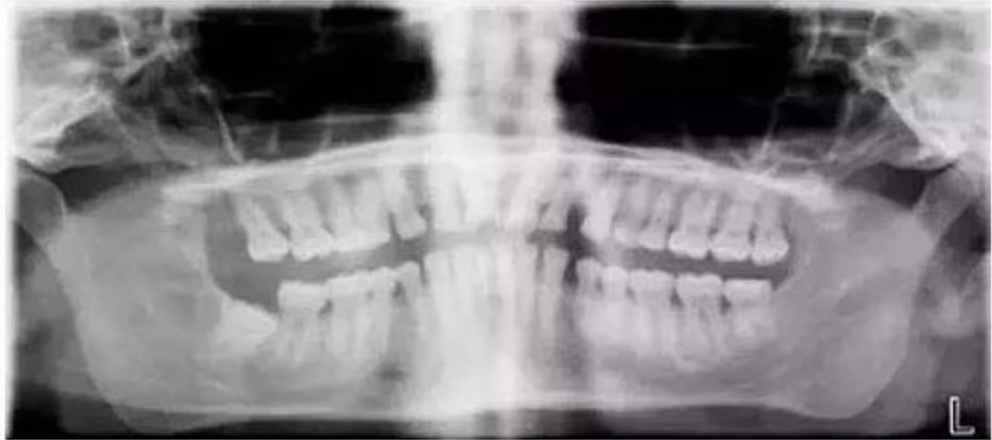

三、牙齿显示较小且双侧脊柱显影过多

【失误原因】

定位聚焦激光束或自动对焦(Autofocus)激光束定位过靠后。影像中牙齿显小且双侧脊柱显影过多。

【解决方法】

将定位聚焦光束前移至侧切牙根尖位置。